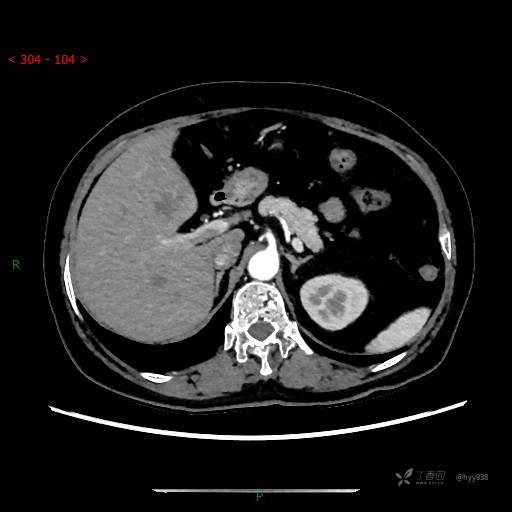

上腹部CT平扫

增强动脉期

静脉期